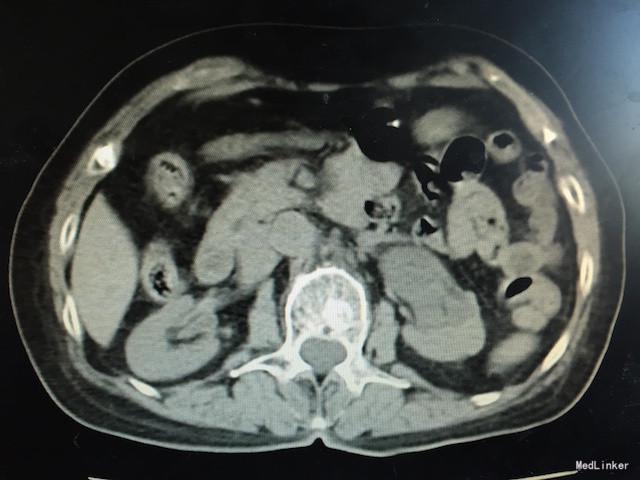

查体:无明显异常。 辅助检查:泌尿系CT如下图所示:左侧输尿管下段可见软组织密度影,其上输尿管、肾盂肾盏明显扩张、积水。腹、盆腔未见明显肿大淋巴结影。考虑输尿管下段软组织肿瘤性病变可能。